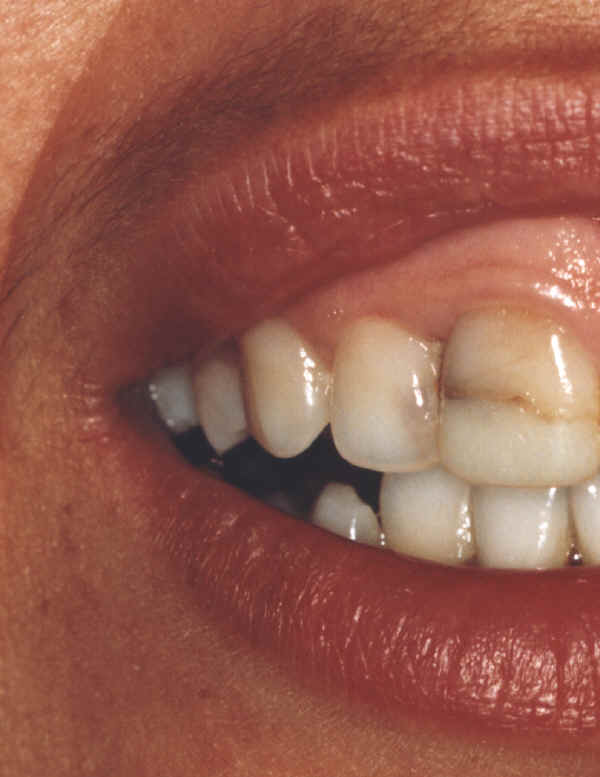

Edição com Montagem Grosseira de Imagens

início

Imagens sem edição

Qual destas imagens não foi editada?

Qual destes lados não foi editado?

Responda, justificando, e receba a resposta com as fotos originais!

Matematicamente a probabilidade de erro na 1ª resposta é igual a 75% = 3/4 x 100

Matematicamente a probabilidade de erro na 2ª resposta é igual a 50% = 1/2 x 100

Não aposte sua prova jurídica nisto, responda e verás!